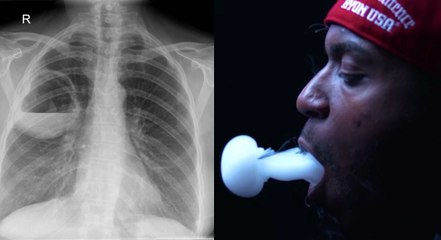

Cigarette électronique : l’origine des lésions aux poumons pourraient avoir trouvé une explication